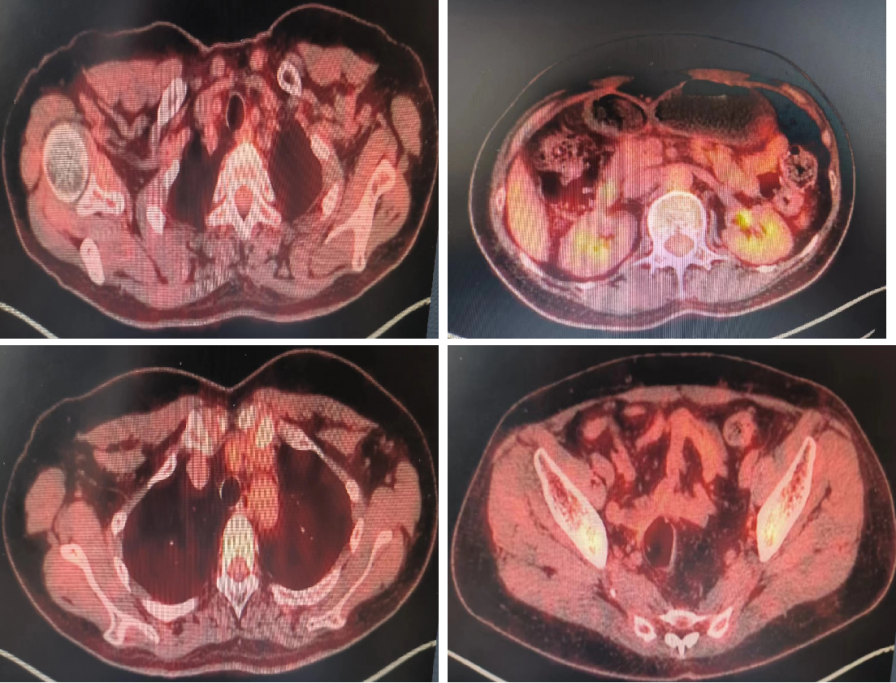

• PET-CT(2021-9-23):左侧锁骨区、左侧腋下、腹膜后多发转移,直乙结肠交界处有病变:子宫及双侧附件术后,局部FDG代谢未见异常增高;直乙结肠交界处肠管管壁增厚,FDG代谢增高,考虚恶性病变,结肠癌或转移瘤;左侧锁骨区多发肿大淋巴结,大者直径约3.13cm,左侧腋下肿大淋巴结,大者直径约2.05cm;腹膜后多发肿大淋巴结,大者直径约4.92cm,FDG代谢增高,考虑淋巴结转移。

1

全身PET-CT:左侧锁骨区、左侧腋下、腹膜后多发转移,直乙结肠交界处有病变